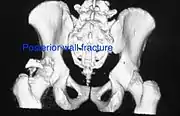

Posterior wallThis is the most common variety of acetabular fracture. It typically occurs due to dashboard injury; when a person travelling in a vehicle involved in a head-on collision, the force applied over the flexed knee travels along the femur bone to the head of the femur, breaking the posterior wall of the acetabulum. The head of the femur is dislocated outside the joint. T shapeWhen a transverse fracture also had a vertical fracture line, it is called a T shape fracture. Here the innominate bone is broken in such a way that all three parts of it, the ilium, the ischium and the pubis are separated from one another. This is a three part fracture. Though both columns are broken, the weight bearing dome is still attached to the main part of the ilium and hence it is not a true fracture of both columns.

• Posterior wall fracture: Iliac oblique and obturator oblique views